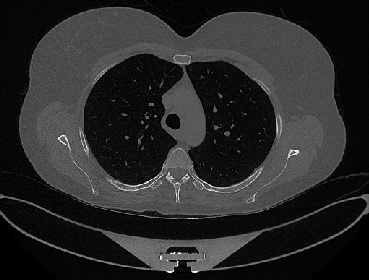

Figure 1 shows four CT scan slices, two from a non-COVID-19 CT scan, on the left and two from a COVID-19 scan, on the right. Bilateral ground glass regions are seen especially in lower lung lobes in the COVID-19 slices.